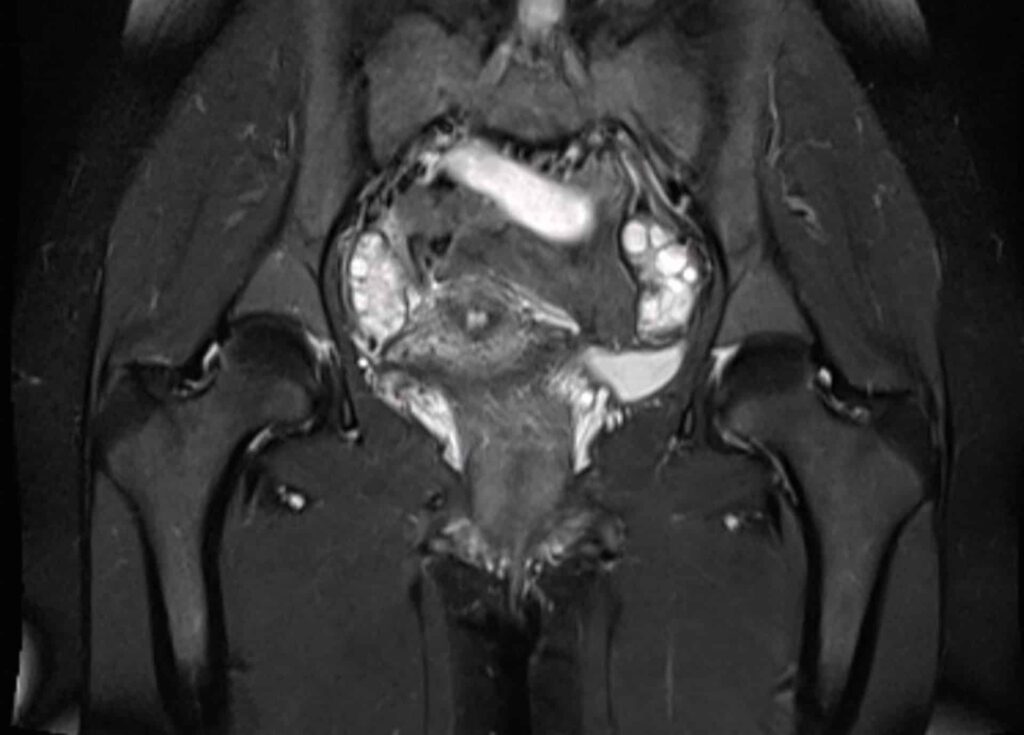

IRM pelvienne L'IRM est un examen non irradiant, sans risque, qui est très utile pour le diagnostic et le bilan d'une endométriose puis Comment se déroule l'examen IRM pelvienne dynamique ?

Dans la plupart des cas d'IRM pelvienne, vous devrez faire un lavement évacuateur quelques heures avant l'examen Comment faire un lavement Evacuateur ? Un lavement évacuateur consiste à injecter par l'anus un liquide dans le rectum ou l'extrémité du. Une préparation digestive par lavement rectal (Microlax) est recommandée afin d'améliorer la qualité des images.

PPT IRM PELVIENNE Pour les nuls PowerPoint Presentation ID5221314. Quels organes Voit-on sur un IRM pelvien ? Qu'est-ce qu'une IRM pelvienne Comment se préparer à une IRM pelvienne ? "En fonction de la demande faite par le médecin généraliste ou spécialiste, le radiologue décidera s'il est nécessaire d'effectuer un lavement évacuateur quelques heures avant l'examen, s'il faut être à jeun (généralement six heures avant l'examen) ou s'il faut avoir une vessie pleine ou vide", répond la spécialiste.

MA 1ERE IRM PELVIENNE ENDOMETRIOSE YouTube. Il est conseillé de réaliser un lavement rectal à domicile au Normacol, idéalement 1 à 3h avant l'examen si possible du Microlax et éventuellement du produit de contraste gadoliné en fonction de l'indication de l'IRM pelvienne.